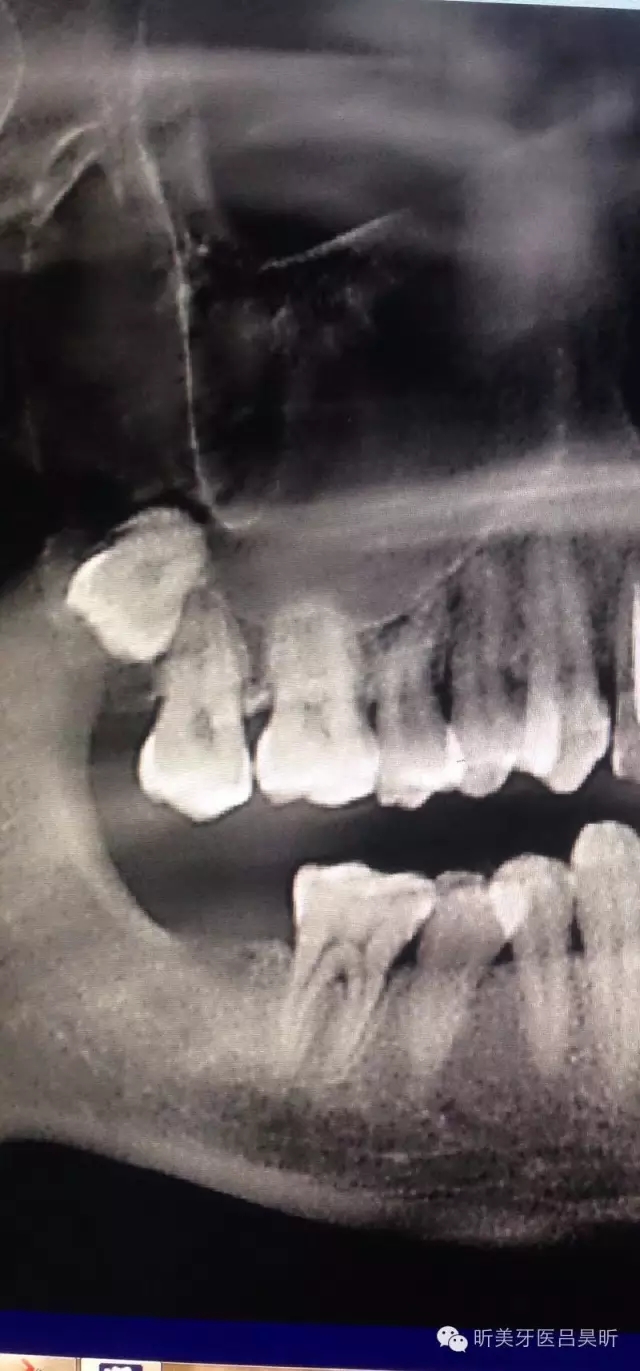

患者,男性,47缺失兩年。

術(shù)前CBCT截圖,垂直骨量似乎感覺(jué)良好

可見(jiàn)種植位點(diǎn)舌側(cè)區(qū)凹陷,牙槽骨上部舌傾明顯。